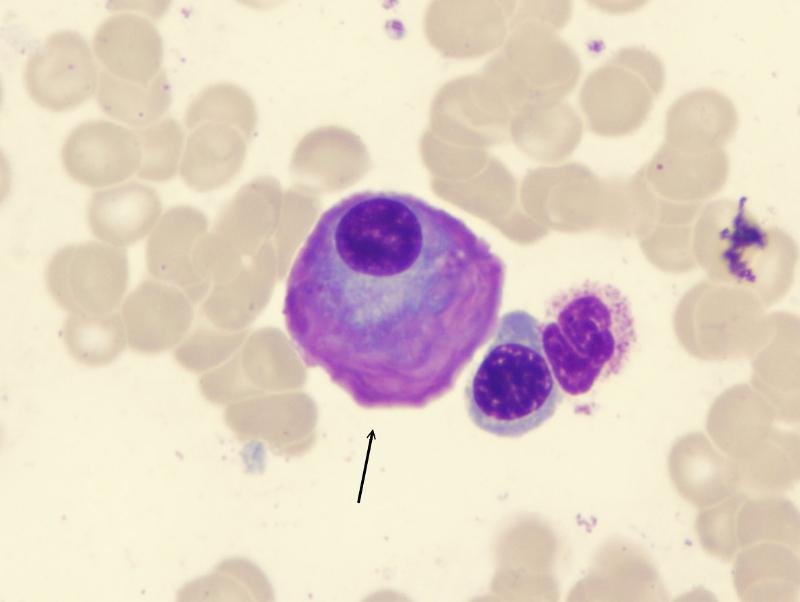

leukocytes

arrow

Plasma

Platelets